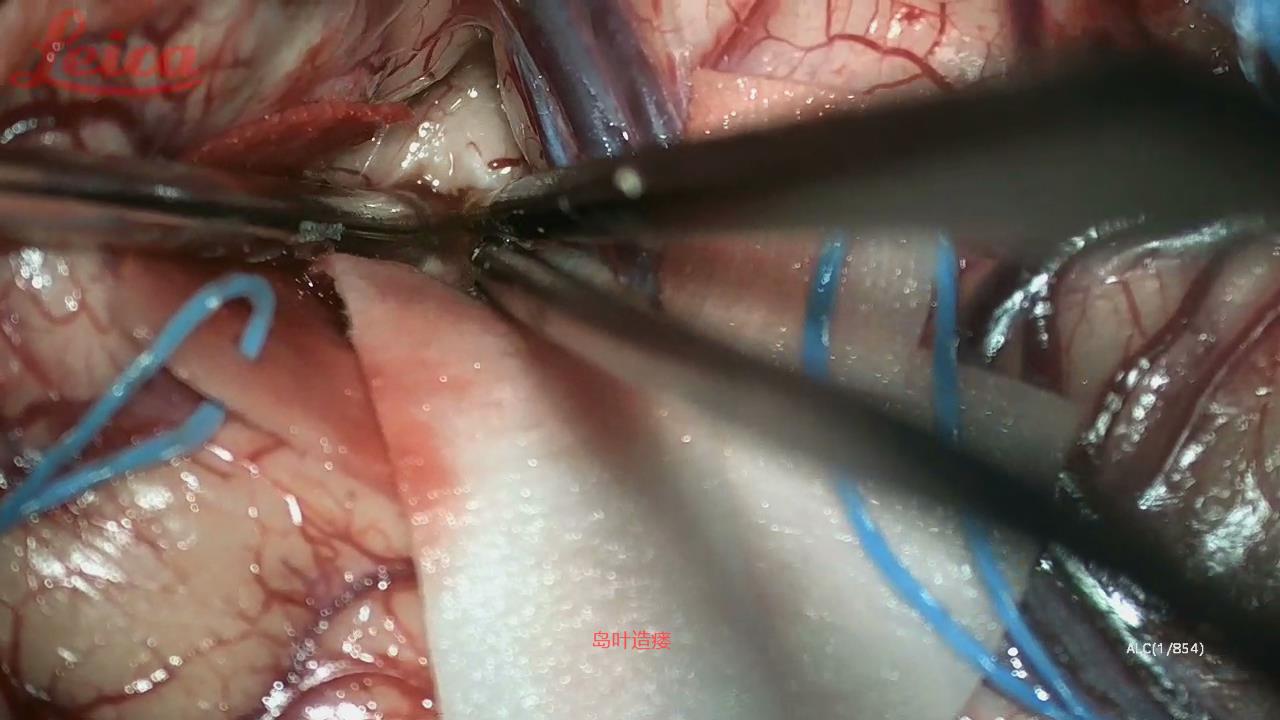

经外侧裂-岛叶造瘘清除血肿简要

经外侧裂-岛叶造瘘清除基底节出血